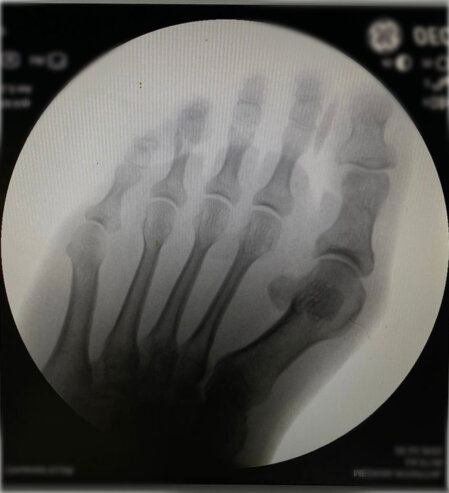

Halluk valgus ayak baş parmağının zaman içerisinde değişik nedenlerle eğilmesi ile ayak yan tarafında çıkıntının da eşlik ettiği bir rahatsızlıktır. Sıklıkla bayanlarda görülmesine rağmen erkeklerde ve çocukluk yaşlarında da karşılaşılmaktadır. Ayağın yan tarafında olan çıktı ve baş parmağın diğer parmakları itmesi ile ayakta şekil bozukluğu ve ağrı oluşur. Bu şekil bozukluğu kişinin ayakkabı giymesinde sıkıntılara neden olabilir.

Tedavisinde ayağın yük veriri pozisyonda çekilen grafileri üzerinde yapılan ölçümlerden sonra hastanın yaşı ve aktivite seviyesine göre kişiye özel planlanmaktadır. Erken dönemlerde ayakkabı modifikasyonu, parmak arası makarası ve gece ateli kullanılmaktadır. Cerrahi gerekliliğe hastanın deformitesinin büyüklüğüne ve hastanın taleplerine göre karar verilmektedir.

Aşağıdaki grafiyi öncesi sonrası şeklinde görmek için farenizi sağ sola hareket ettiriniz.

Yukarıdaki grafileri daha net ve büyük görmek için üzerine tıklayabilir. Sağ üst köşedeki + - tuşları ile daha da büyütebilirsiniz.